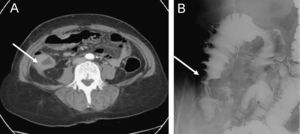

Con el diagnóstico de neoplasia de mama, se envió a la paciente al Servicio de Oncología de nuestro hospital para completar el estudio de extensión y valorar la estrategia terapéutica. Los marcadores tumorales estaban elevados (CEA: 8,8ng/ml [0,0–2,5]; Ca 19/9: 25,8U/ml [0,0–37,0]; Ca 125: 67,0U/ml [0,0–35,0]; Ca 15/3: 249,0U/ml [0,0–29,0]), y en la ecografía abdominal se observó una vesícula biliar pequeña de paredes engrosadas y con imágenes de litiasis en su interior que indicaban una colecistitis crónica litiásica, así como un engrosamiento de la pared del colon derecho. La gammagrafía ósea no demostró alteraciones significativas. Una tomografía computarizada confirmó los hallazgos de neoplasia mamaria y colelitiasis; destacaba, además, el engrosamiento circunferencial de la pared del colon derecho, algún tramo del colon transverso y del recto, con ingurgitación de los vasos sanguíneos circundantes y existencia de pequeños ganglios mesentéricos (fig. 1A).

Ante estos hallazgos, se practicó una colonoscopia que detectó, a la altura del colon ascendente, una lesión polipoidea, sesil, multinodular y friable, cuyo diagnóstico histológico era compatible con adenocarcinoma pobremente diferenciado. El estudio inmunohistoquímico confirmó el diagnóstico de metástasis de carcinoma lobulillar infiltrante de mama (positividad para receptores de estrógenos y citoqueratinas AE1-AE3; negatividad para receptores de progesterona, citoqueratina 20, HercepTest y E-cadherina, índice de proliferación medido con MIB-1 bajo) (fig. 2). Se realizó, además, un enema opaco, que mostró alteraciones radiológicas compatibles con una lesión difusa intramural en el colon ascendente, que podría corresponder a enfermedad metastásica con marcada reacción desmoplástica (fig. 1B).